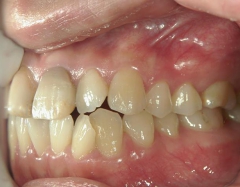

no.37_7548_治療前_右.JPGno.37_7548_治療前_正面.JPGno.37_7548_治療前_左.JPG

no.37_7548_治療後_右.JPGno.37_7548_治療後_正面.JPGno.37_7548_治療後_左.JPG